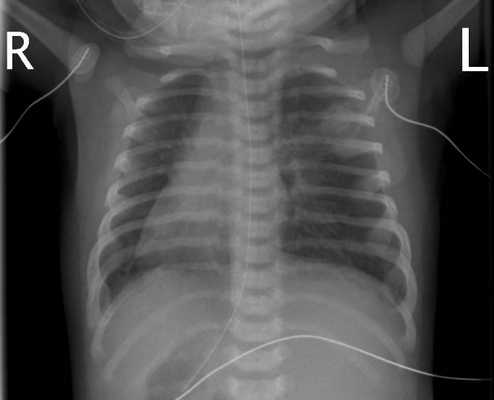

Изображение сердечной тени на рентгенограмме представляется зеркальным отражением нормы

Первое впечатление рентгенлаборанта, что человек стоит спиной к экрану. Сначала его не глядя просят встать передом, а потом возникает мысль о декстропозиции. Старшим детям и взрослым назначаются рентгенографические снимки в прямой и боковой проекции, проводится полное ЭКГ исследование.

- Рентгенография ОГК. На рентгенограмме визуализируется смещение сердечной тени вправо, при комбинированных аномалиях изменяются контуры магистральных сосудов. Чтобы подтвердить транспозицию проводится рентгенография органов брюшной полости.